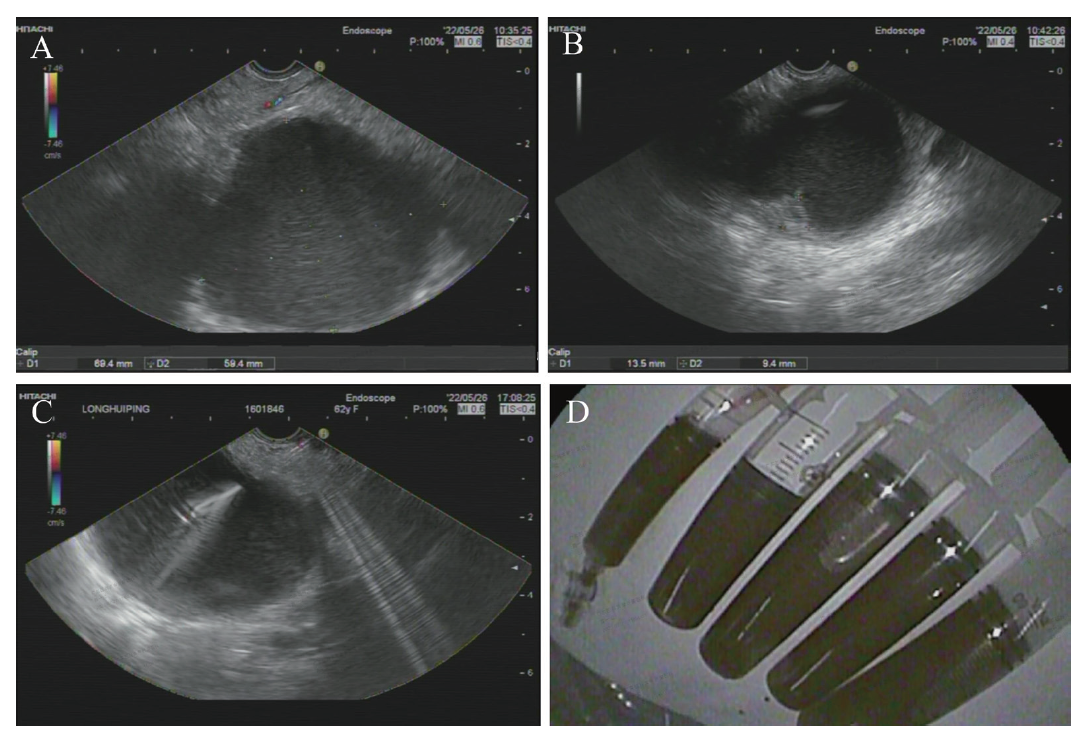

血常规、肝肾功能、血清淀粉酶、癌胚抗原、糖类抗原(CA)19-9、抗核抗体、抗中性粒细胞抗体、风湿因子、甲状腺功能和凝血功能未见异常。外院腹部CT:胰尾见类圆形低密度影,大小57.0 mm×65.0 mm,边界清,增强未见强化,考虑良性病变,假性囊肿可能性大(图1)。

图1 一例PLEC患者外院腹部CT图

注:A为CT平扫冠状位图片,胰尾见类圆形低密度影;B为CT平扫横断位图片;C为CT增强扫描横断位图片,低密度影未见强化;白色箭头所示为低密度影。